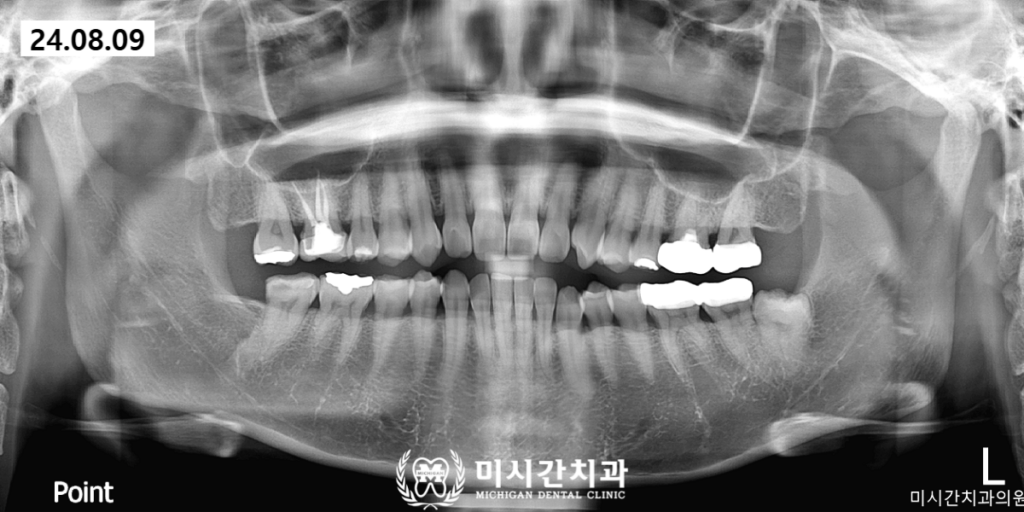

미시간치과에서는 최근 사랑니 부위의

반복적인 붓기와 통증으로 내원하신

환자분의 발치 사례를 성공적으로 마무리하였습니다.

해당 환자분은 사랑니가 잇몸 밖으로

거의 보이지 않는 완전 매복 상태였으며

방사선 사진 촬영 결과 치아가 옆으로

누워 있는 수평 매복 형태를 띠고 있었습니다.

무엇보다 주의 깊게 살펴야 했던 부분은

사랑니 뿌리가 아래턱 신경관과

매우 밀접하게 맞닿아 있다는 점이었습니다.